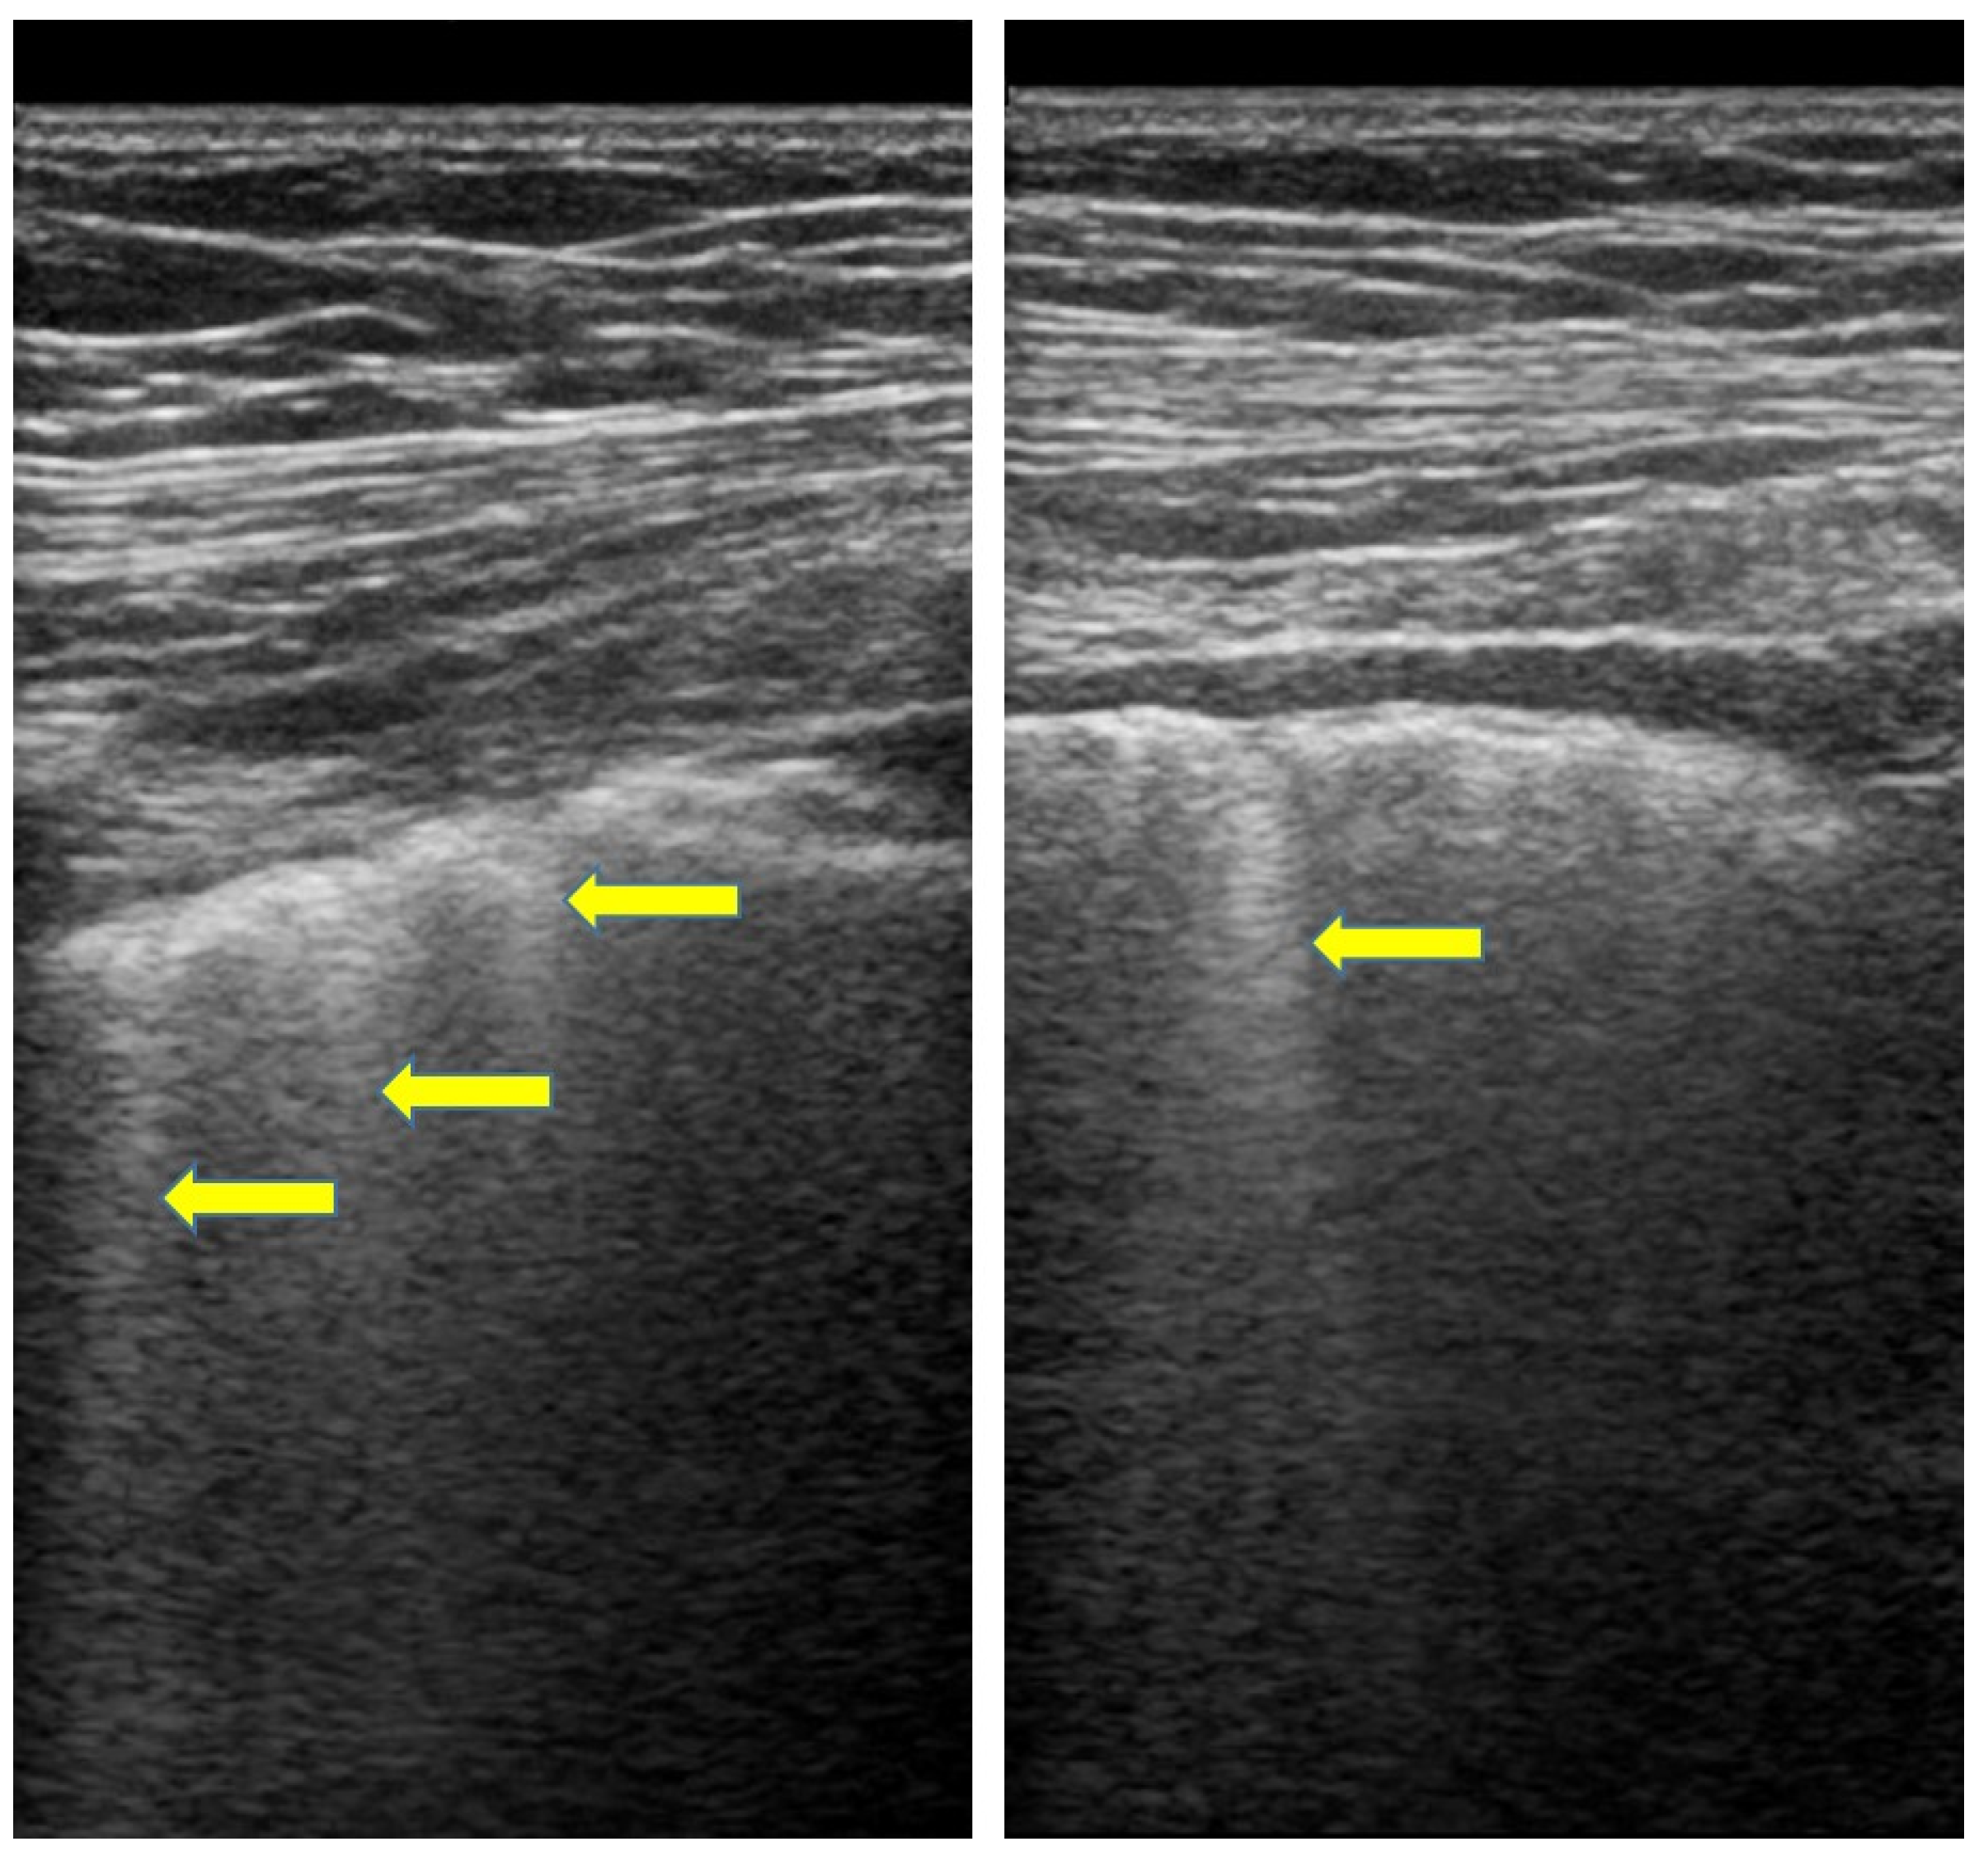

- Gasperini, M.L.; Gigante, A.; Iacolare, A.; Pellicano, C.; Lucci, S.; Rosato, E. The predictive role of lung ultrasound in progression of scleroderma interstitial lung disease. Clin. Rheumatol. 2020, 39, 119–123. [Google Scholar] [CrossRef]

- Ruaro, B.; Baratella, E.; Confalonieri, P.; Confalonieri, M.; Vassallo, F.G.; Wade, B.; Geri, P.; Pozzan, R.; Caforio, G.; Marrocchio, C.; et al. High-Resolution Computed Tomography and Lung Ultrasound in Patients with Systemic Sclerosis: Which One to Choose? Diagnostics 2021, 11, 2293. [Google Scholar] [CrossRef]

- Bruni, C.; Mattolini, L.; Tofani, L.; Gargani, L.; Landini, N.; Roma, N.; Lepri, G.; Orlandi, M.; Guiducci, S.; Bellando-Randone, S.; et al. Lung Ultrasound B-Lines in the Evaluation of the Extent of Interstitial Lung Disease in Systemic Sclerosis. Diagnostics 2022, 12, 1696. [Google Scholar] [CrossRef]